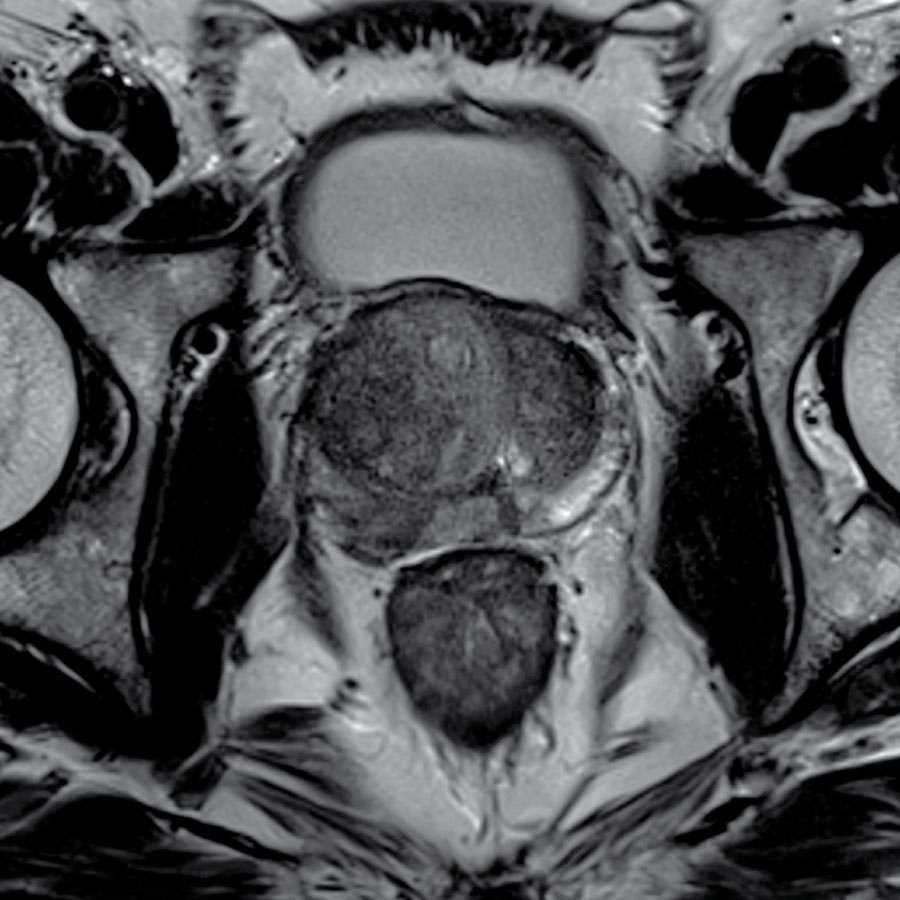

Total Body Imaging

Using 3T MRI technology

Welcome to Kansas City Advanced Diagnostic Imaging Services-Overland Park’s new destination for advanced brain and body imaging. Save time and get the detailed answers you need with our state-of-the-art 3T MRI, featuring 128 channels and a wide bore, which doctors prefer for superior structural detail. We also offer functional imaging for advanced neurological and psychiatric diagnostics. Your scans are interpreted by radiologists with extensive expertise in all imaging modalities. At Kansas City Advanced Imaging, our focus is on providing you with clarity, precision, and peace of mind with every scan.

Our advanced imaging systems provide physicians across specialties with the critical insights needed for effective intervention, surgical planning, and treatment tracking.